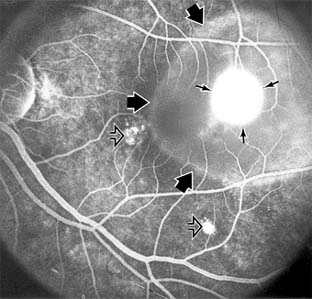

Figure 10-1

Figure 10-1: Age-related macular degeneration with discrete (small arrow) and large confluent (large arrow) macular drusen.

Nonexudative age-related macular degeneration is characterized by variable degrees of atrophy and degeneration of the outer retina, retinal pigment epithelium, Bruch's membrane and choriocapillaris. Of the ophthalmoscopically visible changes in the retinal pigment epithelium and Bruch's membrane, drusen are the most typical (Figure 10-1). Drusen are discrete, round, yellow-white deposits of variable size beneath the pigment epithelium and are scattered throughout the macula and posterior pole. With time, they may enlarge, coalesce, calcify, and increase in number. Histopathologically, most drusen consist of focal collections of eosinophilic material lying between the pigment epithelium and Bruch's membrane; they therefore represent focal detachment of the pigment epithelium. In addition to drusen, clumps of pigment irregularly dispersed within depigmented areas of atrophy may progressively appear throughout the macula. The level of associated visual impairment is variable and may be minimal. Fluorescein angiography demonstrates irregular patterns of retinal pigment epithelial hyperplasia and atrophy. Electrophysiologic testing in most patients is normal.